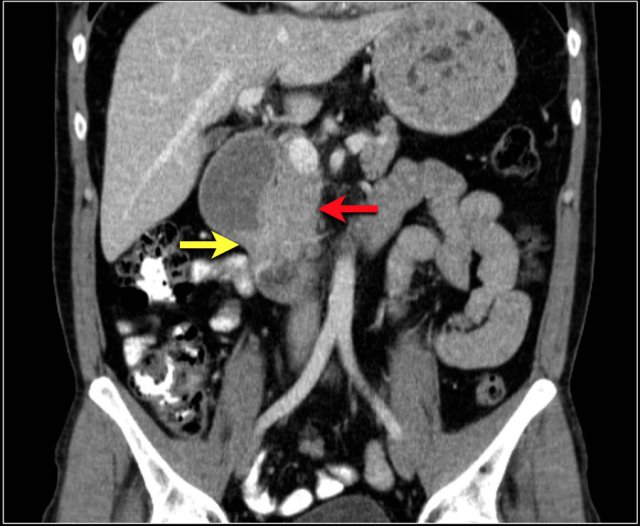

Study the coronal reconstructed CT-image.

Then continue reading.

The findings are:

- Stenotic lesion in the duodenum as a result of an adenocarcinoma (yellow arrow).

- Not possible to separate from the pancreas (red arrow).

- Pre-stenotic dilatation of the duodenum.

The typical imaging representation of a small bowel adenocarcinoma is a focal unilocular, circumferential mass with shouldering of the margins and obstruction.